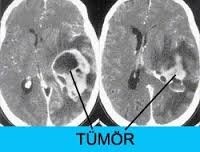

TETKİK VE TEŞHİS

Daha büyük çocuklarda ve yetişkinlerde;

Doktorunuz semptom ve bulguları değerlendirdiğinde hidrosefaliden şüphelenirse tanıyı koymadan önce ayrıntılı bir şekilde hastalığın gidişatını öğrenmeli, ayrıntılı bir fiziksel ve nörolojik inceleme yapmalı, CT veya MRG ile görüntüleme yapmalıdır. Tetkikler sonucunda hidrosefali teşhisi konursa hasta daha ileri tetkik ve tedavi için beyin cerrahi uzmanına refere edilmeli.